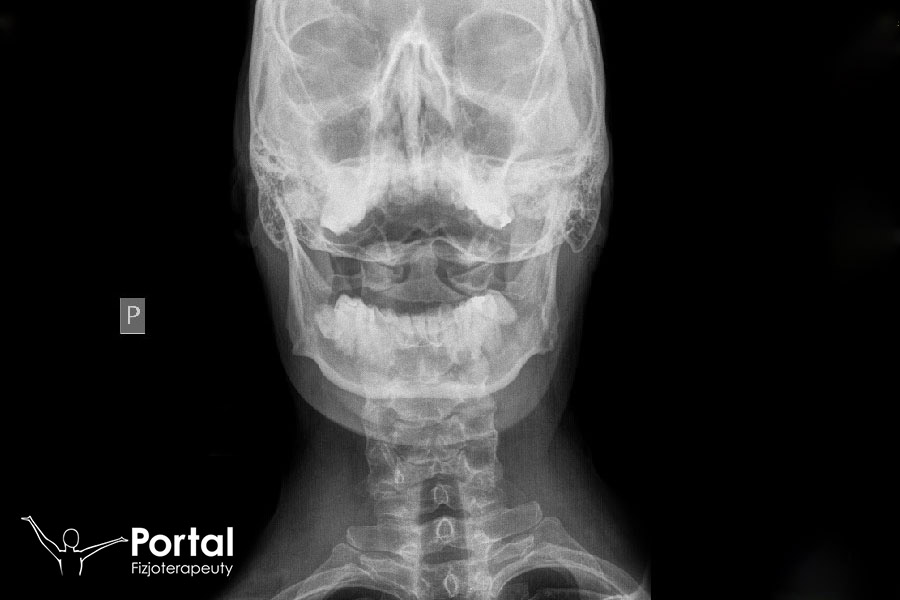

Osteofitoza stanowi jedną z postaci choroby zwyrodnieniowej. Charakteryzuje się tworzeniem narośli kostnych zwanych osteofitami, których obecność nie tylko powoduje dolegliwości